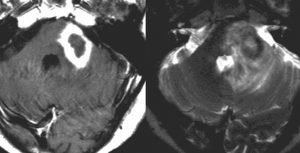

皮膚病変で診断されていた患者さんの同時多発性脳病変

60代女性で,皮膚結節がB cell lymphoma (neoplastic angioendotheliosis)がありました。1年後に急性の認知機能障害と歩行障害がありMRIで発見されたものです。SPECT, PET検査では多発性虚血性病変です。生検手術でIVLの診断が得られました。

左は発症時,右はCHOP化学療法1コース後のT2強調画像です。化学療法で寛解しました。